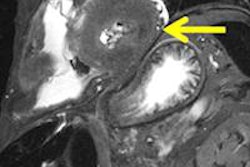

Virtual autopsies continue to attract attention. Authors from Switzerland and Sweden think postmortem cardiac 3-tesla MRI can identify sudden cardiac death in complex cases that are invisible at conventional autopsy. Get the story here.